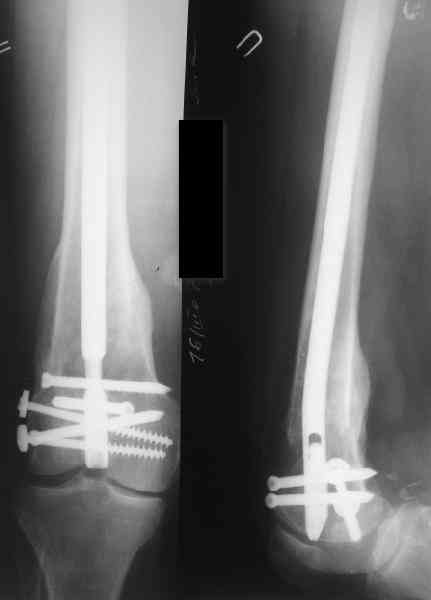

Как обещал, выкладываю рентгенограммы нашего пациента.

Пациенту М., 30-ти лет, 1,5 года назад в одной из московских больниц был выполнен остеосинтез бедренной кости штифтом UFN (диаметр штифта 9 мм).

К нам больной поступил с признаками ложного сустава бедренной кости, перелома

штифта и дистального блокирующего винта (images 1,2,3).

27 марта выполнено удаление блокирующих винтов (сломанный винт пришлось высверливать цапфен-бором), сломанного штифта (дистальный фрагмент удален через канал, образованный разверткой из коленного сустава - image 4),

рассверливание костно-мозгового канала, реостеосинтез штифтом UFN (при проведении штифта в дистальном отломке мы использовали поляризующий винт, диаметр штифта 10 мм). После операции в связи гемартрозом дважды (на 1 и 3 сутки) выполняли пункцию коленного сустава. Сейчас признаков скопления жидкости в полости сустава нет. Послеоперационные рентгенограммы - images 5, 6, 7.